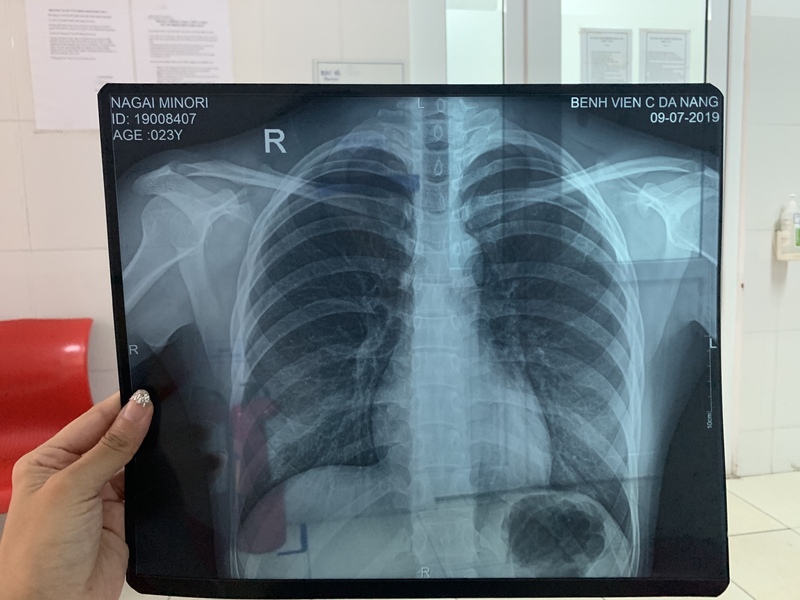

レントゲン

レントゲンは、上半身に何もつけず、

部屋に置かれている(皆が地肌につけて着まわしている)上着を着て立ったまま取ります。

着替えている間とレントゲンを撮る間は誰も入ってきません。

衛生的に上着を着たくなかったのですが上半身裸という恥ずかしさには負けて渋々着ましたが、もう少しどうにかならないのかなと思ったりしました。